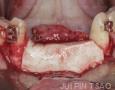

Surgery